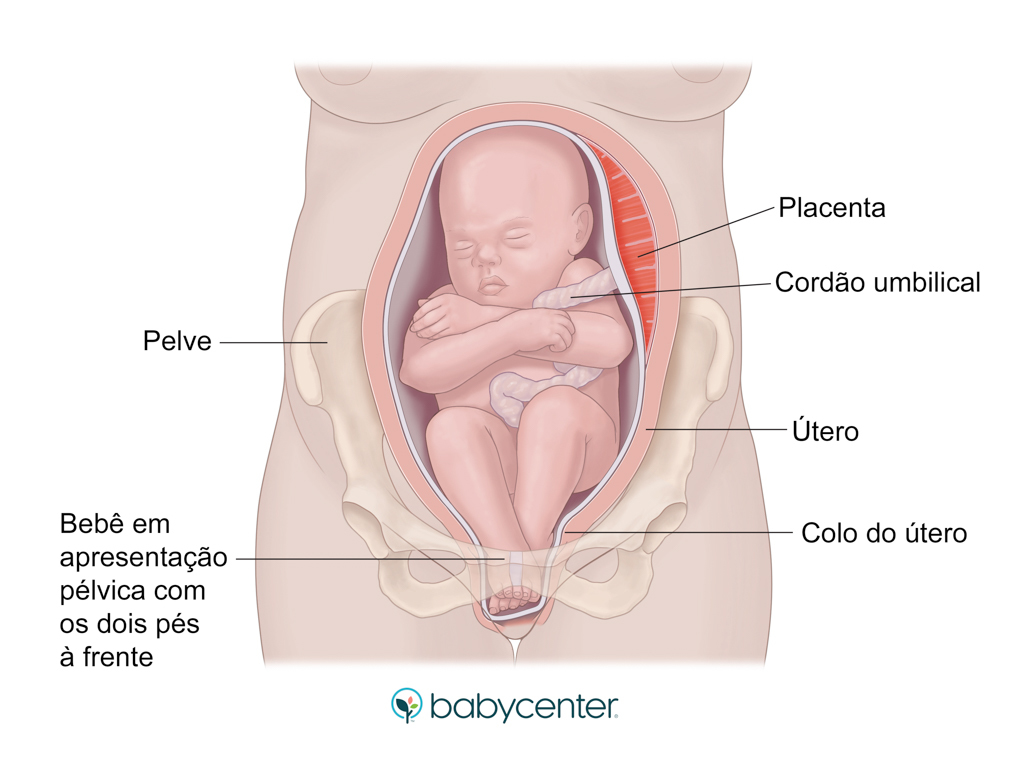

Quando falamos em apresentação pélvica, estamos nos referindo à maneira como o bebê se encaixa no útero, especificamente em relação ao colo do útero. Em vez da posição mais comum, que é a cefálica (com a cabeça para baixo), o bebê pélvico está com os pés ou as nádegas voltadas para a saída. Essa é a grande diferença, e é ela que gera a maioria das preocupações.

Existem diferentes tipos de apresentação pélvica, viu? Tem a pélvica completa, onde o bebê está ‘sentadinho’ com as pernas cruzadas; a pélvica incompleta ou franca, que é a mais comum, com as pernas esticadas e os pés perto da cabeça; e, mais raramente, a apresentação podálica, onde um ou os dois pés estão para baixo. Cada tipo tem suas particularidades e influencia nas decisões médicas.

Além da DDQ, o parto de um bebê sentado na barriga pode apresentar mais desafios. Há um risco ligeiramente maior de prolapso de cordão umbilical (o cordão sair antes do bebê), de lesões durante o parto vaginal e de um parto mais demorado. Por isso, a equipe médica sempre avalia com muito critério a melhor via de nascimento.

Para confirmar, a ultrassonografia é a ferramenta mais precisa. Ela não só verifica a posição exata, como também avalia o tipo de apresentação pélvica, a quantidade de líquido amniótico e a localização da placenta, informações vitais para planejar os próximos passos. Um bom diagnóstico é o primeiro passo para um plano de parto seguro.